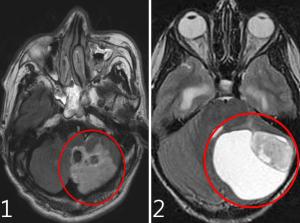

시각자극 아닌 신경·뇌·혈관 이상 등은 치료 필요드물게 뇌종양·뇌경색 등 심각한 질환에서도 발생어지럼증은 두통과 더불어 신경과를 찾는 환자가 호소하는 가장 흔한 증상 중 하나다. 대부분 경과가 양호한 편이지만 간혹 어지럼증 자체가 중요한 신경학적 질환의 한 증상일 수 있으므로 원인 질환에 대한 정확한 진단이 필수적이다. 특히 가만히 있거나 길을 걷다가, 잠자리에서 자고 일어날 때 갑자기 어지러움이 발생한다면, 게다가 속이 울렁거리고 걸을 때 휘청거리거나 물체가 두 개로 보인다면 전문의와의 상담이 필요하다.